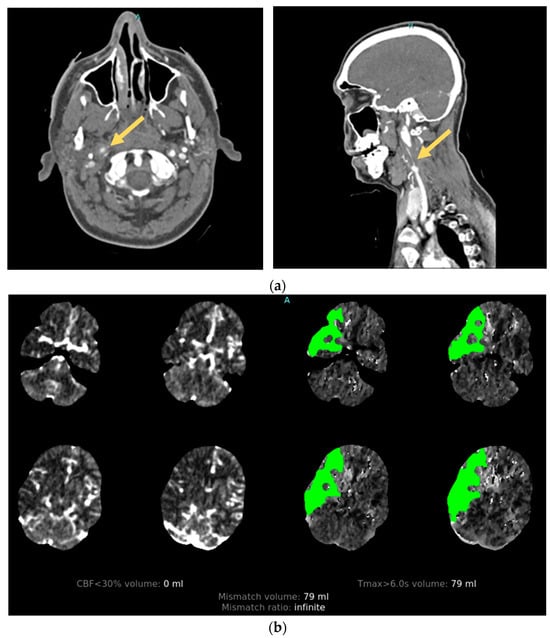

3.3. Vessel Imaging

3.3.1. Angiography

- Hopyan, J.J.; Gladstone, D.J.; Mallia, G.; Schiff, J.; Fox, A.J.; Symons, S.P.; Buck, B.H.; Black, S.E.; Aviv, R.I. Renal safety of CT angiography and perfusion imaging in the emergency evaluation of acute stroke. Am. J. Neuroradiol. 2008, 29, 1826–1830. [Google Scholar] [CrossRef] [PubMed]